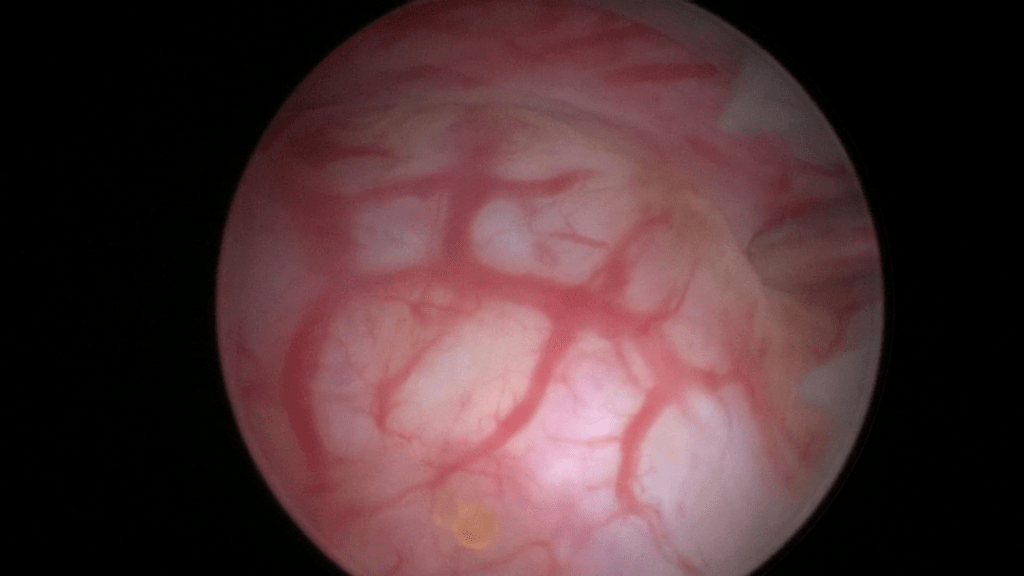

Final image of the mid-urethra after creating four depots of Bulkamid® at the 12, 3, 9 and 6 o’clock positions.